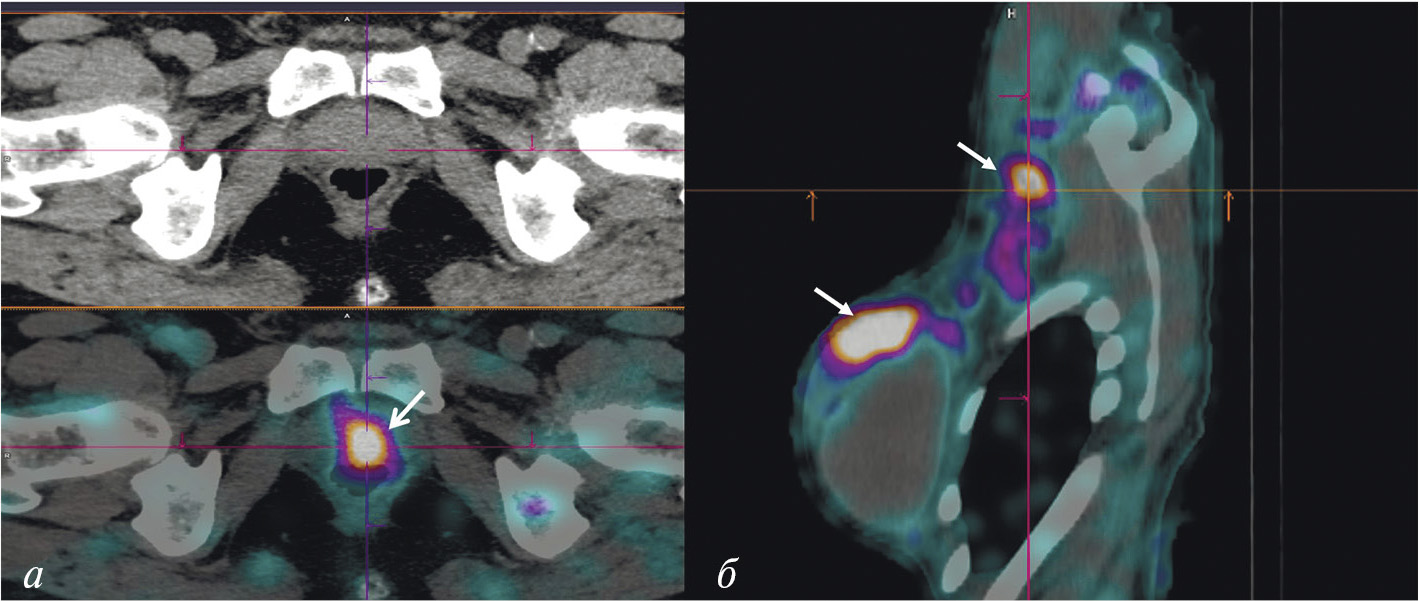

В мировой ядерной медицине для сцинтиграфии обычно применяют 111In-пентетреотид, или 111In-октреотид ([111In-DTPA]octreotide, OctreoScan, Tyco Healthcare, США; АО “Фармсинтез”, Россия). Основные показания к его использованию — стадирование, рестадирование и мониторинг лечения нейроэндокринных SSTR-позитивных опухолей. В последние годы 111In-пентетреотид служит для радионавигации при хирургическом лечении новообразований с гиперэкспрессией соматостатиновых рецепторов. К сожалению, физические характеристики индия-111 (длительный период полураспада, неоптимальный для регистрации на гамма-камере спектр излучения, высокая стоимость циклотронного производства) ограничивают его применение в радионуклидной диагностике. В связи с этим не подвергается сомнению актуальность создания в России меченного технецием-99м октреотида для ОФЭКТ-диагностики нейроэндокринных опухолей. Разработкой такого радиофармпрепарата в рамках проекта федеральной целевой программы “Фарма-2020” занимался ТПУ в сотрудничестве с НИИ онкологии Томского НИМЦ. Клинические испытания отечественного 99mТс-октреотида продемонстрировали его высокую эффективность при диагностике и стадировании НЭО (рис. 3). В настоящее время набор для приготовления этого РФЛП зарегистрирован в России под названием “Нейроскан, 99mТс”, а его производство налажено в ТПУ.

Рис. 3. ОФЭКТ/КТ с 99mТс-октреотидом пациента с нейроэндокринным раком лёгкого: а — конгломерат первичной опухоли и метастазов в лимфатические узлы; б — метастазы в кости; в – селезёнка